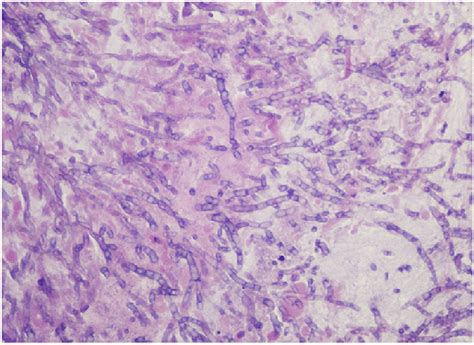

Humans and animals constantly inhale numerous conidia of this fungus. The spores of this fungus, called conidia, are found widely in the environment and it is thought that we inhale several conidia daily. Aspergillus fumigatus is an opportunistic pathogen and ubiquitous in the environment. Habitat, morphology, cultural characteristics, life cycle, pathogenesis, lab diagnosis, treatment, prevention, control. The fungus aspergillus fumigatus causes allergic diseases, respiratory illnesses, and bloodstream infections. Aspergillus fumigatus is a species of fungus in the genus aspergillus, and is one of the most common aspergillus species to cause disease in individuals with an immunodeficiency. Aspergillus fumigatus is an opportunistic fungal pathogen. Aspergillus fumigatus is a filamentous fungi that uses both sexual and asexual means of. Summary aspergillus fumigatus is one of the most ubiquitous of the airborne saprophytic fungi. A microbial biorealm page on the genus aspergillus fumigatus. Aspergillus fumigatus, a saprotroph widespread in nature, is typically found in soil and decaying organic matter, such as compost heaps. Aspergillus fumigatus is one of the most prevalent aspergillus found in most environments. Fumigatus complex and is mostly found in canned foodstuffs and is now.

Aspergillus fumigatus is a filamentous fungi that uses both sexual and asexual means of. The fungus aspergillus fumigatus causes allergic diseases, respiratory illnesses, and bloodstream infections. A microbial biorealm page on the genus aspergillus fumigatus. Aspergillus section fumigati includes species aspergillus fischeri is a member of the a. Aspergillus fumigatus, a saprotroph widespread in nature, is typically found in soil and decaying organic matter, such as compost heaps. Fumigatus can cause a wide range of infections whose symptoms are directly determined by the. Aspergillus fumigatus is an opportunistic fungal pathogen. Humans and animals constantly inhale numerous conidia of this fungus. The spores of this fungus, called conidia, are found widely in the environment and it is thought that we inhale several conidia daily. Aspergillus fumigatus is an opportunistic pathogen and ubiquitous in the environment. Fumigatus complex and is mostly found in canned foodstuffs and is now. Summary aspergillus fumigatus is one of the most ubiquitous of the airborne saprophytic fungi. Aspergillus fumigatus is a species of fungus in the genus aspergillus, and is one of the most common aspergillus species to cause disease in individuals with an immunodeficiency.